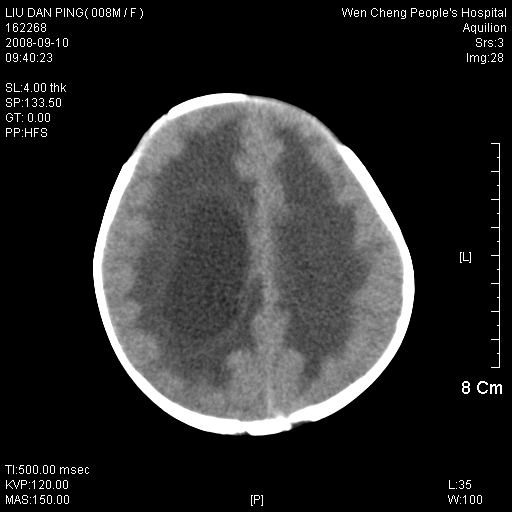

以下是引用卜一在2008-9-10 16:21:00的发言:[br]髓母细胞瘤伴梗阻性脑积水!支持![br]髓母细胞瘤特点:—般直径大于3.5cm,位于后颅凹中线之小脑蚓部。累及上蚓部的肿瘤延伸到小脑幕切迹之上,ct平扫肿瘤多呈均匀一致的高或等密度病灶,增强检查呈均匀一致的强化。病灶中有小坏死时,平扫亦可呈不均匀之混杂密度,注药后有增强。[br]

以下是引用zjzjr在2008-9-10 15:09:00的发言:[br]髓母细胞瘤伴梗阻性脑积水.